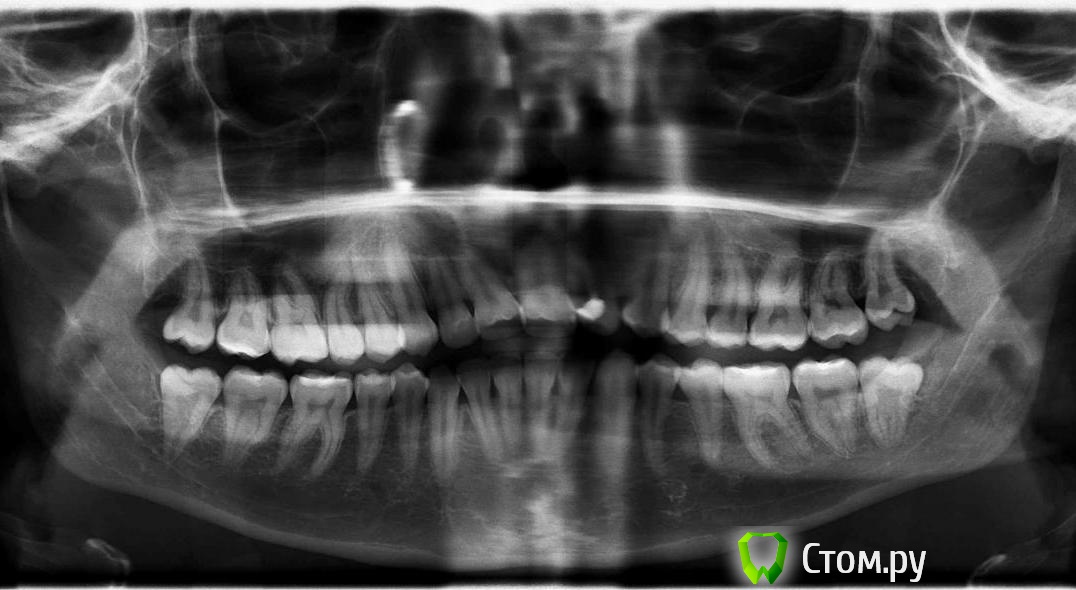

son-leta Опубликовано 25 марта, 2014 Поделиться Опубликовано 25 марта, 2014 Здравствуйте, дорогие врачи Меня замучил один зуб, который в последнее время активно ноет то от горячего чая, то от холодного воздуха. Сейчас боль весьма ощутима. Именно этот зуб (36) вытворяет такое уже лет 6 с разной периодичностью, обычно редко. Когда говорила про него врачам, они смотрели и отвечали, что всё хорошо. В нём стоит пломба (но начал ныть ещё до неё), внешне всё хорошо. Что посоветуете? Снимок прилагается (он годичной давности, но мало что изменилось) Ссылка на комментарий

son-leta Опубликовано 1 апреля, 2014 Автор Поделиться Опубликовано 1 апреля, 2014 После посещения врача картина яснее не стала. Боли прошли несколько дней назад и пока не возвращались. Сделали свежий снимок, врач сказала, что картины воспаления нет, пломба стоит хорошо, не к чему придраться, показаний для депульпации тоже нет.. странный зуб Ссылка на комментарий